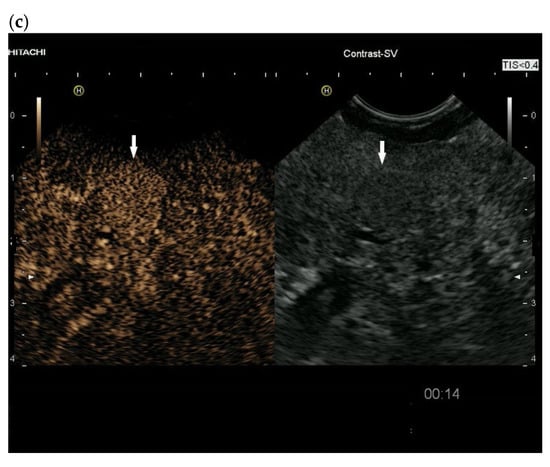

3.4. CEUS and CH-EUS

| Cases | CEUS | CH-EUS | ||

|---|---|---|---|---|

| Arterial Phase | Venous Phase | Arterial Phase | Venous Phase | |

| RCC metastases [83] (n = 4) | Hyperenhancement, Early | Hyperenhancement | ||

| RCC metastases [61] (n = 3) | Hyperenhancement, homogeneous pattern | Slow washout | ||

| RCC metastasis [86] (n = 1) | Hyperenhancement, Inhomogeneous pattern | No washout | ||

| Melanoma metastasis [63] (n = 1) | Iso- to slightly hypoenhanced | Hypoenhanced | ||

| Melanoma metastasis [87] (n = 1) | Isoenhanced | Hypoenhancement of the peripheral rim, central non-enhancement | ||

| Melanoma metastasis [61] (n = 1) | Isoenhanced, heterogeneous | Fast washout | ||

| SCLC metastasis [83] (n = 1) | Hyperenhancement | Rapid washout | ||